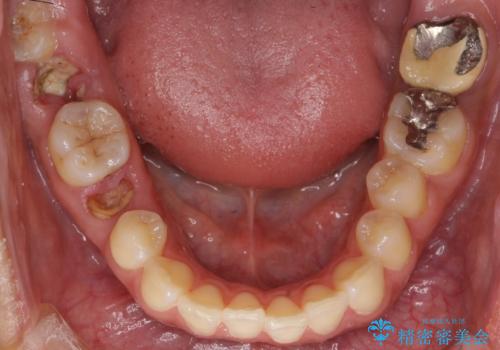

- 歯が折れてなくなってしまったことを主訴に来院された患者様です。

精査したところ、右下の奥歯2本(右下75)は大きなう蝕により歯冠が崩壊し保存不可能な状態でした。